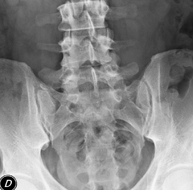

- RX Columna lumbar

Técnica mediante la cual, utilizando rayos X, se obtienen imágenes de la columna lumbar para su estudio.

- RX Pelvis

Procedimiento mediante el cual, utilizando rayos X, se obtienen imágenes de la pelvis para su estudio, especialmente de los huesos pélvicos.